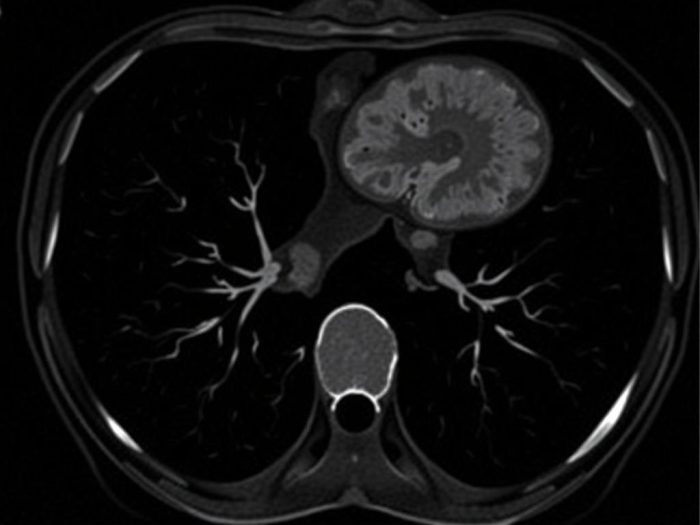

КТ печени с контрастом — это простой на вид, но важный инструмент в руках врача. Он помогает увидеть структуру органа, отличить доброкачественное образование от злокачественного…